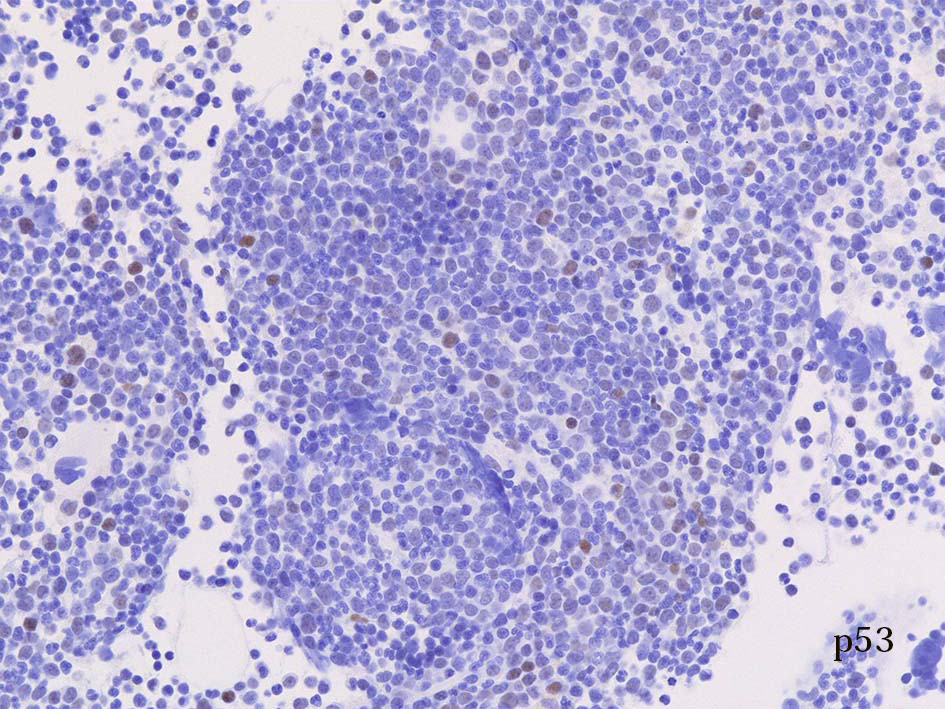

- p53染色

MDS/MPNの大多数の症例にはp53陽性細胞が出現する.一方, conventionalなMPNにはまずp53陽性細胞は出現しない.

atypical CMLではminor componentであってもp53+細胞が出現する. p53陽性細胞のないaCMLはない. (伊藤雅文先生談)

CMLでは, p53+になることがあるが、その場合は, accelerated phaseかBC(blastic crisis)である.

BCでは, ほとんどがp53陽性になる.(accelerated phaseかBCかを区別することがp53染色で可能)